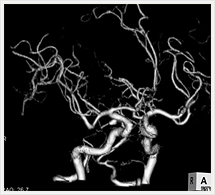

画像紹介

CTでは輪切り像の他にも立体的な画像(3D画像)を作成することもできます。そのためにはより細かくキレイな画像を撮影しなければなりません。当院では64列CTを導入しており、キレイな画像をより細かく撮影することができます。その画像を元に3D画像を作成することによって、より正確な手術のシミュレーションが可能になります。実際に手術をしたときの様子が、手術をする前に画像として見らます。外科系の手術には欠かせない技術となっておりますが、内科系でも血管内手術にも多く利用されております。

当診療放射線技術科では毎日各診療科に対して、その手術に最適な3D画像を提供しております。

以下にその3D画像を一部分紹介します。

頭部